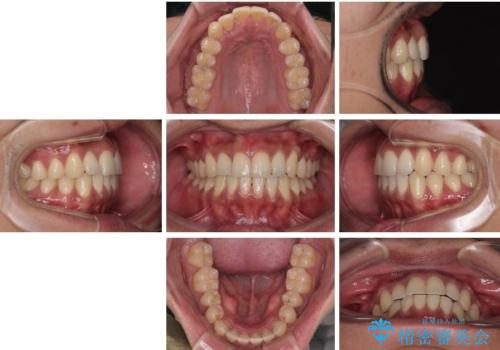

診察したところ、上下顎前歯部に軽度の叢生(ガタつき)が認められます。

目立たない装置を希望されたのでインビザライン ライトパッケージで治療を行うことになりました。